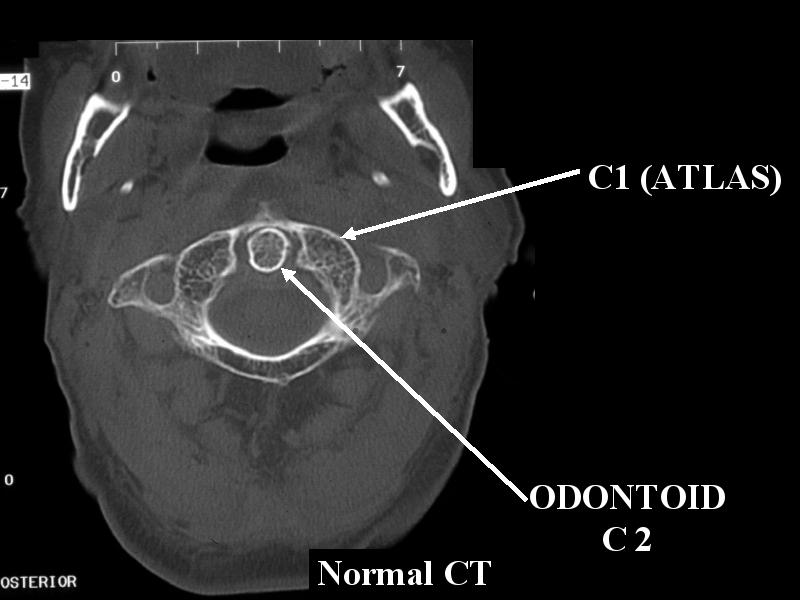

ER 151 C2 FX